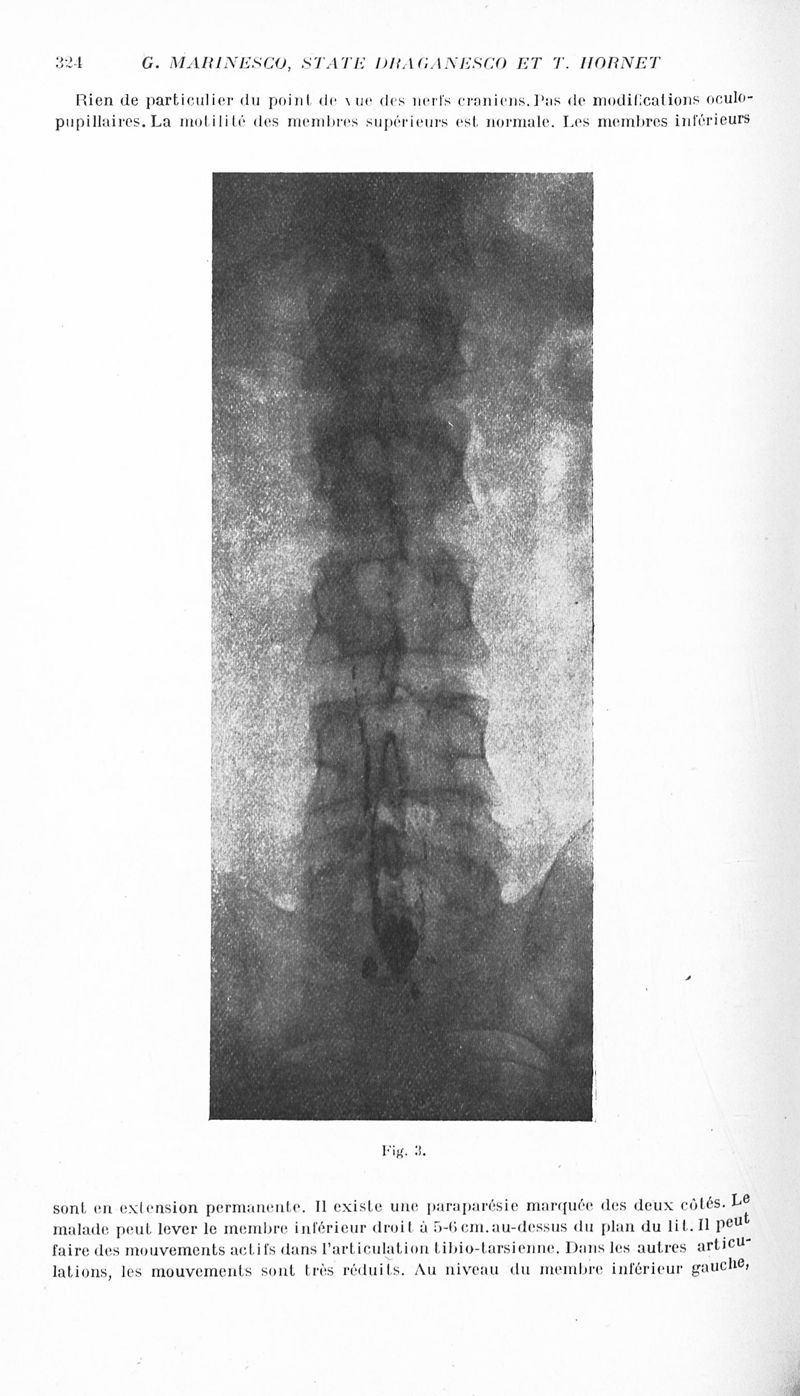

Revue neurologique

1934, vol 1. - Paris : Masson , 1934.